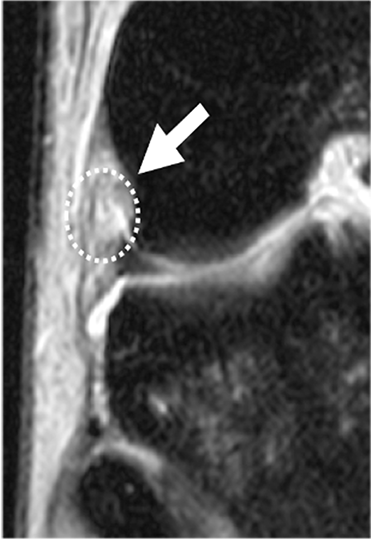

Intra-articular injuries mainly include medial or lateral meniscal injuries. More specific lesions, such as those of the medial meniscal ramp and the meniscal roots, in particular of the external meniscus, are also experienced (29,30) (Figure 7). Cartilage injuries should also not be overlooked because they are important for the long-term outcome of the knee. The prevalence of medial meniscal ramp injuries is estimated at 15.5–24% (29,31,32).

Meniscal root injuries also play a role in the rotational instability of the knee, in particular external meniscal root injuries (35,36). The prevalence of external meniscus root injuries ranges from 6.6%– 13.5% (30,37). These injuries should be diagnosed and treated simultaneously (Figure 8).

In this rotatory instability, there are varying extra-articular lesions of the anterolateral structures and posteromedial capsular plane. Lesion assessment of the medial plane must include both the meniscotendinous complex of the semimembranosus and the medial meniscotibial ramp. The semimembranosus is likely to be involved in the physio-pathogenesis of a medial meniscal ramp injury because of its anatomical relationship with the posterior segment of the medial meniscus and the meniscotibial ligament (33). Thus, according to Hughston, the reflex contraction of the semimembranosus during trauma from excessive anterior tibial subluxation secondary to ACL rupture stresses the posteromedial capsule while the meniscus is trapped between the femur and tibia, leading to tears in the meniscocapsular and/or meniscotibial ligaments (34). These lesions correlate with a high-grade pivot shift so it is important to look for and include them in surgical planning to restore the rotational kinematics of the knee (32).